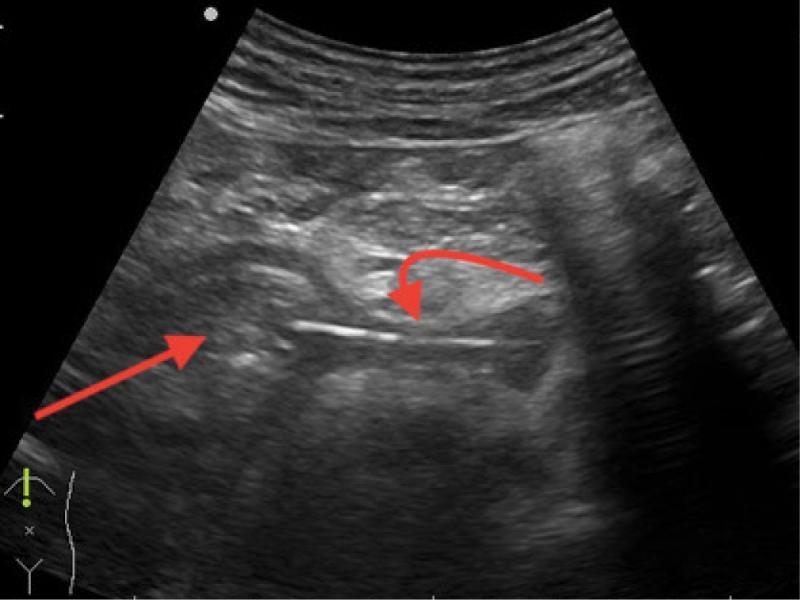

Because of improvement in his condition and for personal reasons, the patient delayed the EUS-related hospitalization for nearly two weeks, showing up asymptomatic and with normal laboratory results on the day of admission. It was then that a transabdominal US scan was performed, showing a linear hyperechoic object (40 mm in length) extending from the gastric antrum wall (muscular layer), and heading through the retroperitoneal site in the direction of the pancreatic body, surrounded by a dense fluid collection. The findings were consistent with the presence of a foreign body (Fig. 1). The patient was once again asked about his medical history and recent symptoms. Initially, he could not recall any probable situation of ingesting a foreign body.

Fig. 1.

Transabdominal ultrasound, Aloka Alpha Prosound 6, straight arrow: stomach (pyloric part) transverse view, curved arrow: toothpick